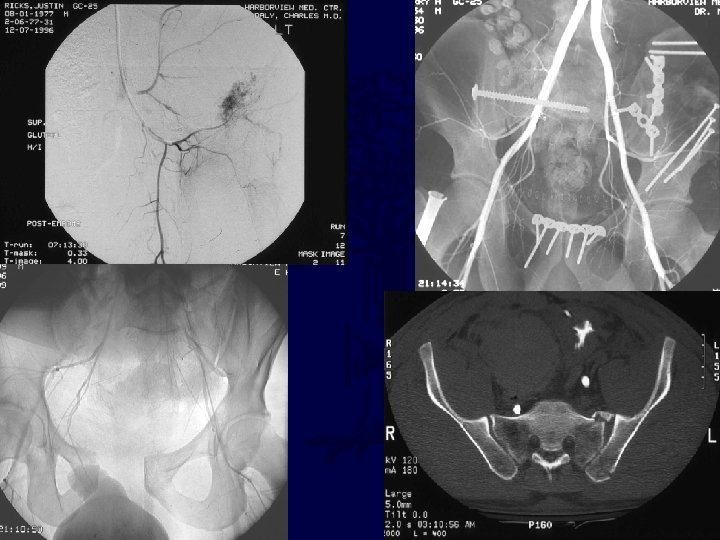

Role of Angiography? ? ? • Valuable for arterial only • Estimated at 5 -15% • Timing (early vs late? ) • Institution dependent

Role of Angiography? ? ? • Fracture pattern may predict effectiveness • Contrast CT suggests • Effective in retrospective studies!!!

Vascular Injuries • Arterial vs Venous vs Cancellous • Unstable posterior ring association • Associated fracture extension into notch • Role of angiography Cryer et al, JT, 1988 O’Neill et al, CORR, 1996 Goldstein et al, JT, 1994

Retrospective evidence Hypotensivesuggests… with stable pelvic pattern… • • Proceed to Laparotomy (85% with abdominal hemorrhage) • Hypotensive with unstable pelvic pattern… • Proceed to Angio (59% with positive Eastridgeangio) et al, JT, 2002 Contrast enhanced CT very suggestive of arterial source (40 fold likelihood ratio) (PPV and NPV of 80%, 98%) Stephen et al, JT, 1999